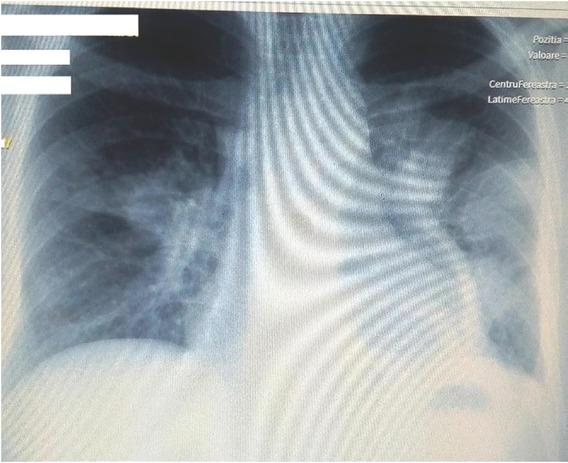

Under wide-spectrum antibiotic treatment (with ampicillin/ sulbactam 4.5 g/daily and Levofloxacinum 1000 mg/daily), his general condition partially improved, but he was still presenting nocturnal subfebrile values (37.3ºC–37.8ºC) and mild chest pain. Chest X-ray was repeated after 7 days from admission and revealed a big oval cavity of 13 cm in the left inferior lobe; previous lesions have grown in size (Figure 2).

Chest X-ray after 7 days: a big oval cavity image of 13 cm in the left inferior lobe; previous lesions have grown.